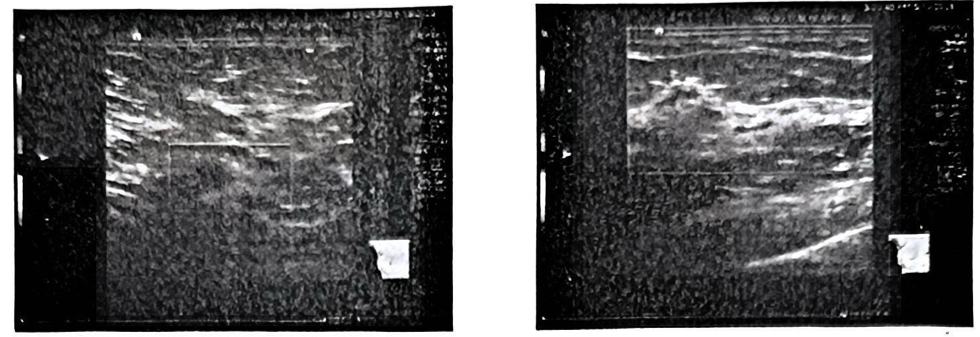

图2 2025年6月 淋巴结、乳腺超声(右腋窝低回声淋巴结较前无明显变化;左乳腺Ca术后,左前胸壁未见明显异常;右乳腺未见占位性病变[BIRADS分类:1类];双颈部、双锁骨下、左腋窝、双腹股沟未见明显异常肿大淋巴结)